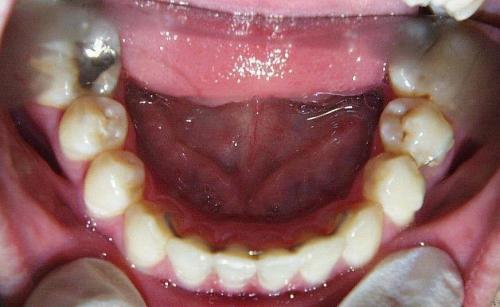

Vor der Behandlung